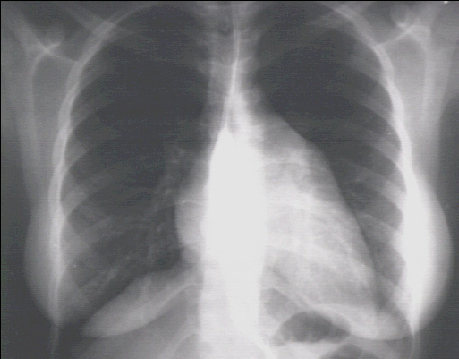

Left Ventricular Enlargement + Left Atrial Enlargement PA and Lat

These chest X rays show left ventricular enlargement and left atrial enlargement.

This PA view demonstrates the enlarged left ventricle as an increase in the inferolateral cardiac border associated with an increased cardiothoracic ratio . The markedly enlarged left atrium is manifested by the double contour within the heart border, an elevated left mainstem bronchus, and an enlarged left atrial appendage.